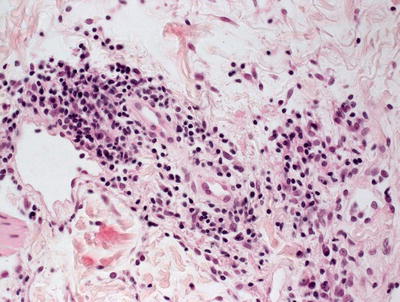

Histologic changes of erythema chronicum migrans are those of a superficial and deep perivascular lymphohistiocytic infiltrate with no overlying epidermal changes [52–54] (Fig. 5.14). Characteristic findings include the presence of plasma cells, especially in biopsies taken from the periphery of the lesions. Some authors have described increased eosinophils in biopsies taken closer to the center of the lesions [53, 55]. A perineural infiltrate of lymphocytes and plasma cells has also been described in biopsies of erythema chronicum migrans (Fig. 5.15) [56]. An interstitial inflammatory infiltrate is also seen in some cases. In these situations, abundant histiocytes have been identified [57, 58]. Special stains for microorganisms and polymerase chain reaction testing can be used to identify borrelial microorganisms in the majority of cases.

Fig. 5.15

Scattered plasma cells are present within the inflammatory infiltrate in most cases of erythema chronicum migrans